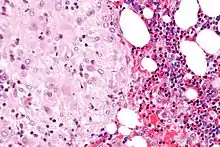

У базальній оболонці морфологічно розрізняються три шари:

- Зовнішній компактний шар (stratum compactum);

- Проміжний губчастий шар (stratum spongiosum);

- Граничний базальний шар (stratum basalis), що прилягає до міометрію.

Там де синцитіотрофобласт пошкоджений, у децидуальній оболонці утворюються випадкові відклади фібриноїдів. Ділянка відкладення на місці зіткнення трофобластів з компактним шаром називається «шаром Рора», у місці між компактним і губчастим шарами — «шаром Нітабух» (при вростанні плаценти останній відсутній)[2].

На початку вагітності децидуальна оболонка являє собою потовщений до 1 см ендометрій з розрослими залозами і великими децидуальними клітинами (cellulae deciduales), що містять глікоген. Окрім того, децидуальні клітини з'являються в матці і в другій частині менструального циклу: так звана менструальна децидуальна оболонка (decidua menstrualis), що відпадає в період менструації.

Базальна децидуальна оболонка утворює материнську частину плаценти. Шари її, звернуті до плода (компактний і губчастий), руйнуються ворсинами хоріона, на їхньому мсці утворюються лакуни, заповнені кров'ю. Глибокі шари утворюють базальну пластинку, від якої до хоріона відходять перегородки, що ділять лакуни на окремі камери. Крайкова зона базальної оболонки утворює замикальну пластинку плаценти.